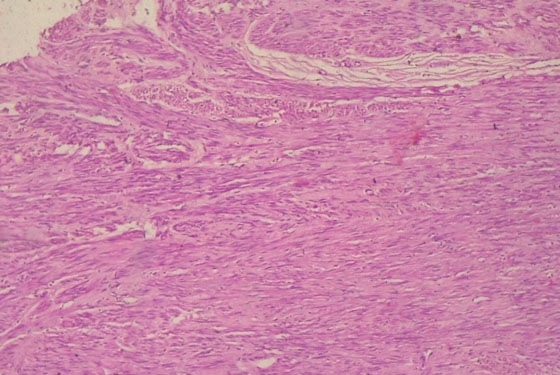

Histology of the left ovary revealed thyroid follicles, cholesterol clefts, and focal areas of multifollicular proliferation with follicular cells exhibiting vesicular nuclei and no features of malignancy, confirming a benign germ cell tumor, specifically SO (Figure 5).

Figure 5: Histology showing struma ovarii.

Share Image:

Our case is unique and interesting because our patient, who was 70 years old, presented with a large, multiloculated, multiseptate cystic ovarian mass, which had soft tissue masses and hemorrhagic ascitic fluid two decades after the menopause, which are all the features associated with ovarian malignancy [9]. Distinguishing between SO and ovarian carcinoma before surgery can be difficult, as the symptoms and clinical presentation are identical [10]. Most cases of SO are diagnosed during histopathologic examination following surgery [9], as exemplified by our patient. Macroscopically, the tumor is usually solid or, as seen in our patient, cystic, with solid areas or protrusions, while on microscopy, it is composed of mature thyroid tissue consisting of colloid follicles of various sizes [10].